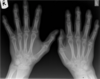

**Psoriatic arthropathy** Pencil in cup X-ray showing some of changes in seen in psoriatic arthropathy. Note that the DIPs are predominately affected, rather than the MCPs and PIPs as would be seen with rheumatoid. Extensive juxta-articular periostitis is seen in the DIPs but the changes have not yet progressed to the classic 'pencil-in-cup' changes that are often seen.